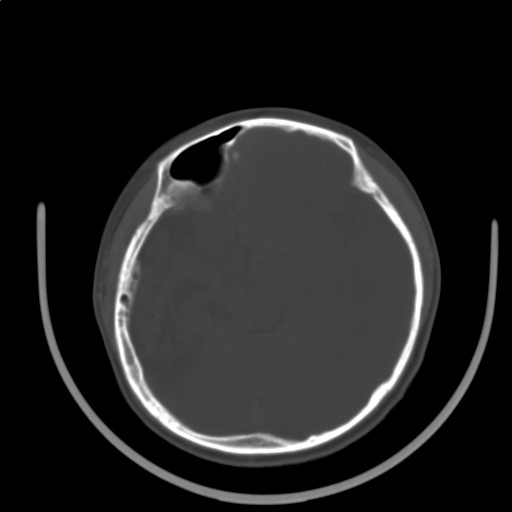

标题: PED3416:F,12Y,智力下降,学习成绩差,8个月时发过高烧。

右侧半球萎缩,软化,多量脑回样钙化,考虑颅面血管瘤病,建议dsa检查

右侧半球萎缩,软化,多量脑回样钙化,同侧颅盖板障增宽,考虑颅面血管瘤病,建议dsa检查与化脓性脑膜炎后遗改变鉴别。